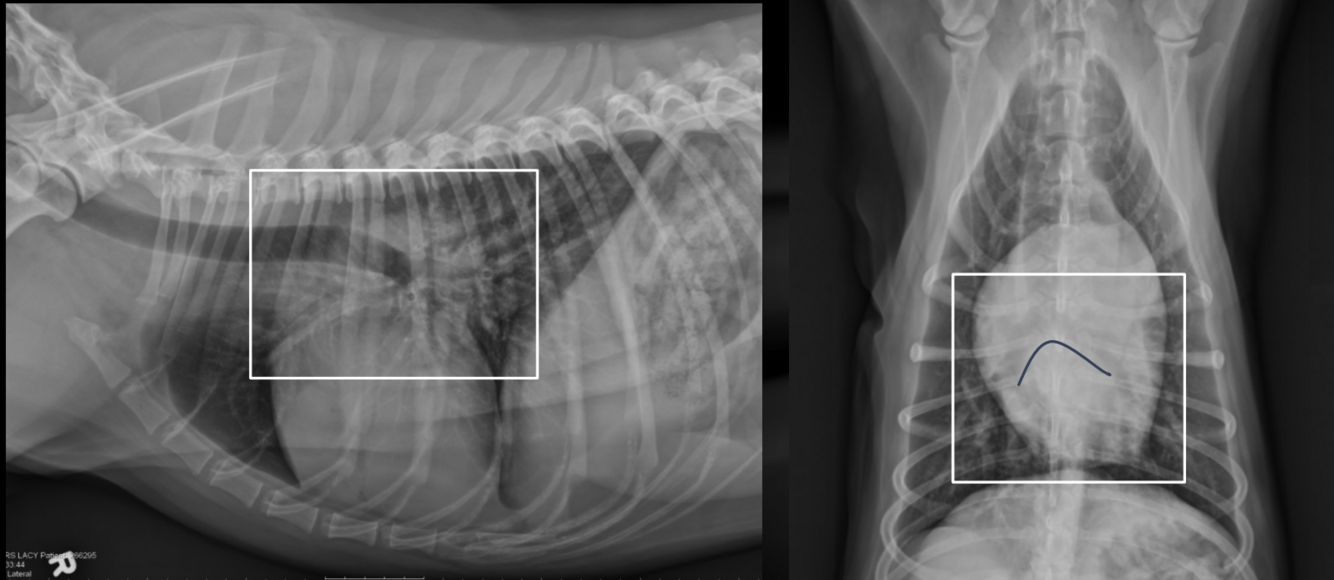

What is shown in these images?

A

cranioventral mediastinal mass

-pushes heart caudally

-pleural effusion seen in VD view